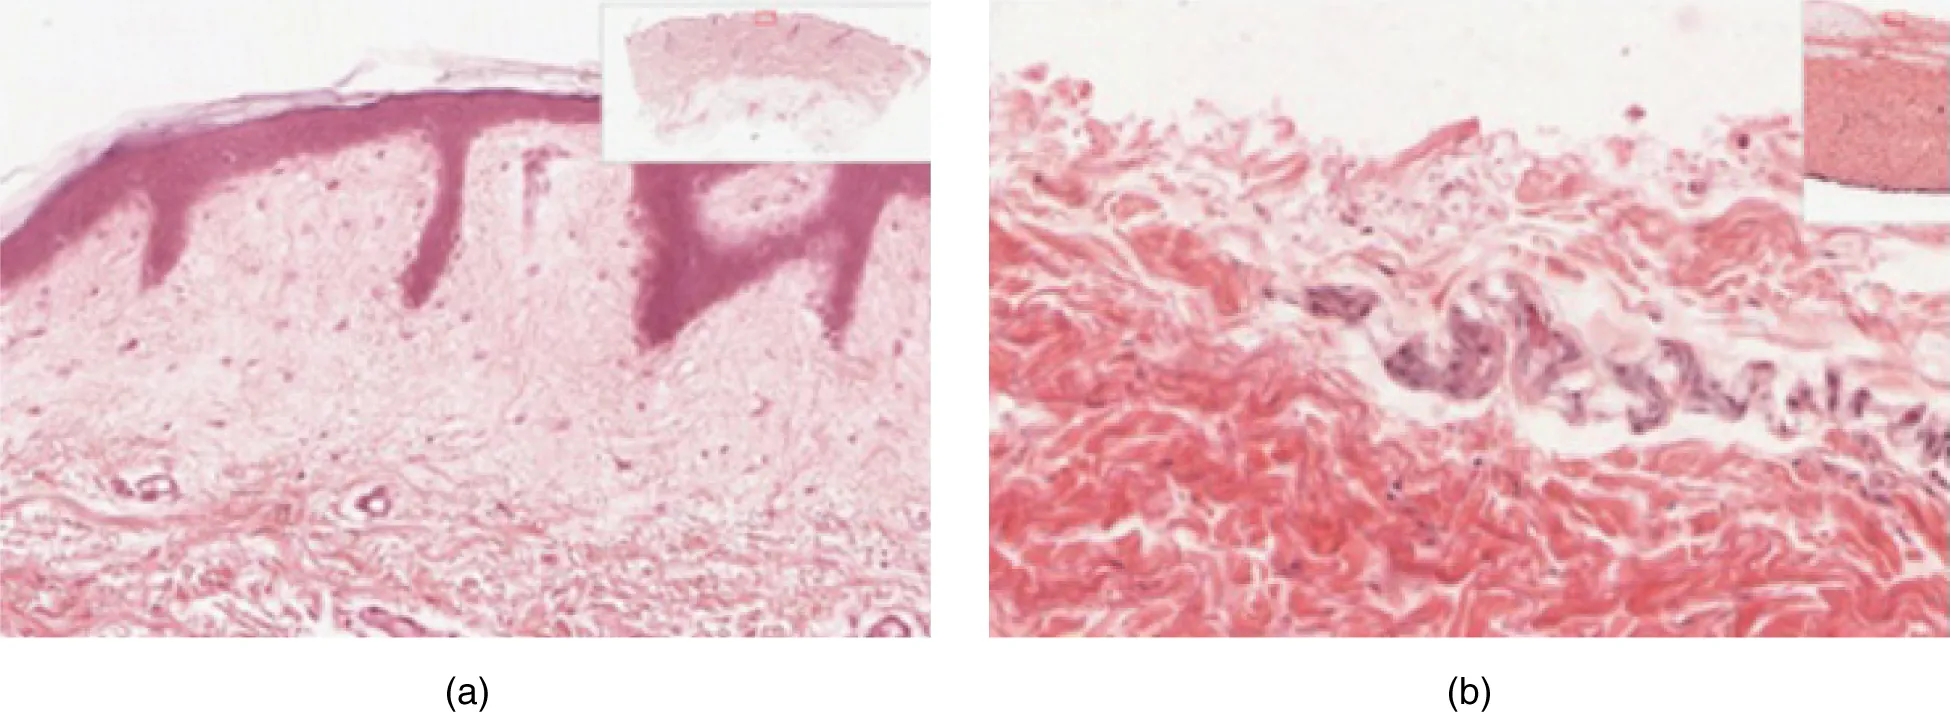

The cells in all of the layers except the stratum basale are called keratinocytes. A keratinocyte is a cell that manufactures and stores the protein keratin. Keratin is an intracellular fibrous protein that gives hair, nails, and skin their hardness and water-resistant properties. The keratinocytes in the stratum corneum are dead and regularly slough away, being replaced by cells from the deeper layers (Figure 5.4).

The outer layer of cells in this micrograph is the thinnest layer and stained deep purple due to full keratinization of dead cells. The next layer occupies one quarter of the micrograph, is lightly stained, and is a dense collection of cells. The third layer from the top is mostly white, with lightly stained, loosely-packed strands radiating in random directions. The bottom-most layer is densely-packed, with thick bands of highly organized muscle tissue that are darkly stained.

Figure 5.4 Epidermis The epidermis is epithelium composed of multiple layers of cells. The basal layer consists of cuboidal cells, whereas the outer layers are squamous, keratinized cells, so the whole epithelium is often described as being keratinized stratified squamous epithelium. LM × 40. (Micrograph provided by the Regents of University of Michigan Medical School © 2012)